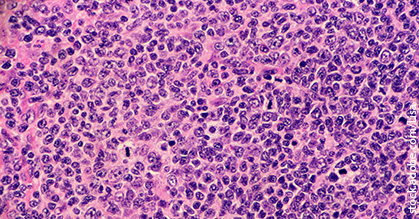

While outcomes for patients with follicular lymphoma are generally good, better options are still needed for those who relapse. Unfortunately, there are fewer options for patients with marginal zone lymphoma.